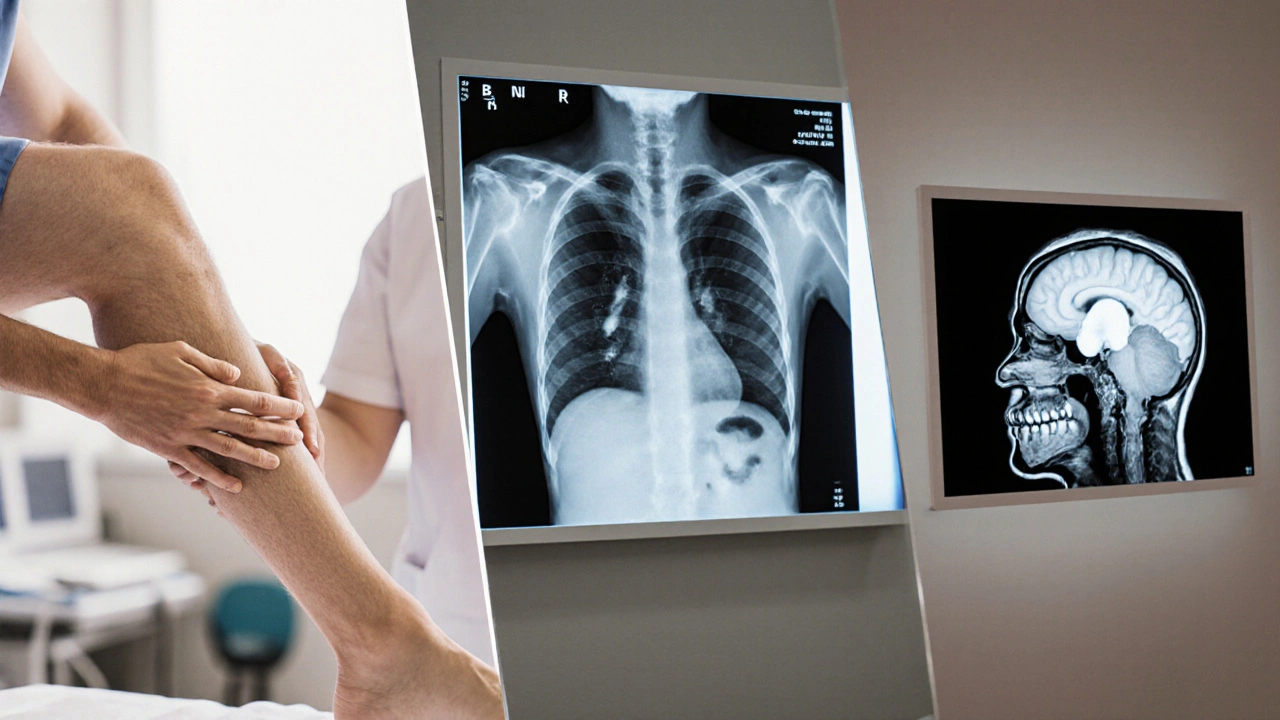

- Pulmonary edema: Rapid, shallow breaths, a feeling of drowning, or a wheezy cough that produces frothy pink sputum are red flags. Listening with a stethoscope reveals crackles at the lung bases.

- Cerebral edema: New or worsening headache, vomiting, blurred vision, or difficulty walking suggests the brain is swelling. Prompt imaging (CT or MRI) is essential.

- Imaging - chest X‑ray for pulmonary edema, ultrasound of veins for deep‑vein thrombosis, MRI for cerebral edema.